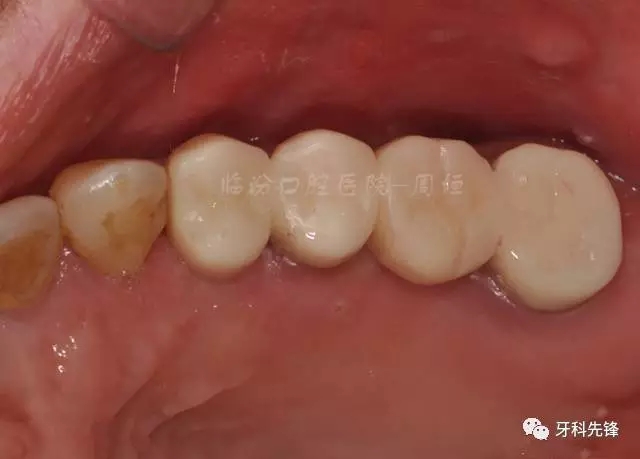

圖29術(shù)后頰面照

640.webp (33).jpg